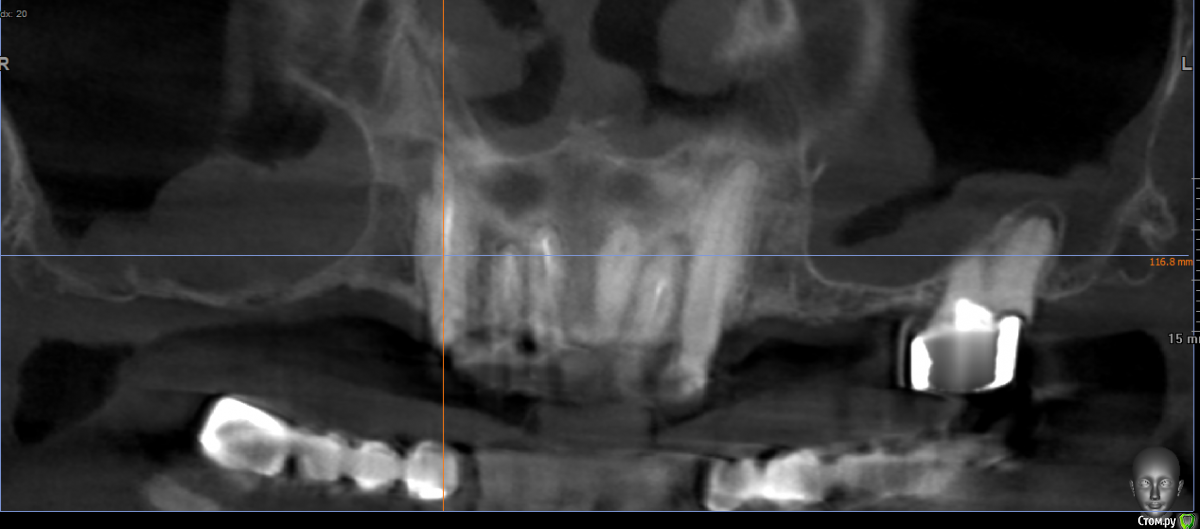

kramer Опубликовано 15 мая, 2019 Поделиться Опубликовано 15 мая, 2019 Коллеги, здравствуйте. Нужен совет. Ситуация: пациентка 70 лет (родственница), давно носила бюгельный протез, и вот одному из опорных зубов пришел конец. КТ ниже, фотографии завтра добавлю. Рассматриваю вариант изготовления несъемного протеза на 4 имплантатах. Опыта все-на-4 нет. Поэтому хотелось бы по крайней мере собрать информацию, возможна ли такая опция. Особенно волнует 2 момента: 1) Отсутствует вертикальная атрофия альвеолярного отростка во фронтальном отделе. Линия улыбки низкая. Предположим, окончательный протез будет м\к или циркон. Означает ли это, что редукцию кости делать необязательно? (правда там и редуцировать особо некуда). 2) В области 14 и 24 ширина гребня 3,5-4 мм. Что делать с этим? Оставлять пришеечную часть винта не покрытым костью небно или пытаться каким-то образом конденсировать кость? 14122224 Ссылка на комментарий

Дмитрий Л. Опубликовано 15 мая, 2019 Поделиться Опубликовано 15 мая, 2019 Вы не написали когда нагружать планируете.Щечно мало кости. Зубы не факт что легко удалятся. Я бы рассмотрел такой вариант:1. Удаление центральных и боковых резцов; удаление моляра. Имплантация в обл. премоляров. 2. От клыка до клыка временный мост. Бюгель перебазировать или сделать ЧСПП. Перерыв два месяца. 3. Имплантация в области резцов. Перерыв 6 месяцев. 4. Протезирование в укороченной дуге. Ссылка на комментарий